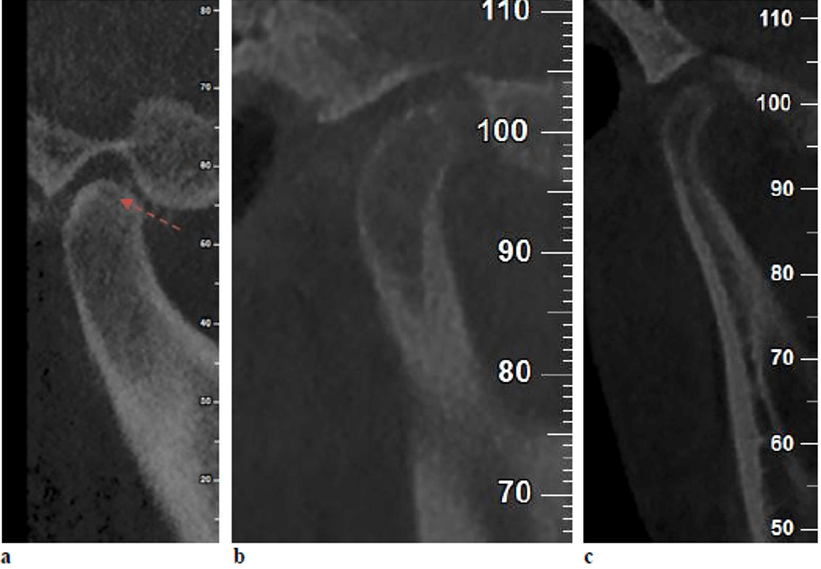

Estudios previos han informado que varios pacientes con trastornos de la ATM podrían sufrir cambios anatómicos en los tejidos óseos y/o blandos de la articulación temporomandibular. La anatomía de la ATM podría evaluarse mediante diversas técnicas, entre ellas la radiografía panorámica, la radiografía transcraneal, la tomografía computarizada de cone beam (TCCB) y la resonancia magnética (RM). La TCCB es una modalidad fiable para la evaluación de los defectos óseos de la ATM y esta es comparable a la tomografía computarizada (TC) en cuanto a precisión. Las imágenes de la ATM obtenidas mediante TCCB pueden proporcionar mucha información sobre los cambios óseos, incluyendo osteofitos, erosión, aplanamiento, esclerosis del hueso subcondral, anquilosis y seudoquistes.

En cuanto a los cambios óseos, no se encontraron diferencias significativas entre los pacientes con disfunción temporomandibular y los grupos asintomáticos en el presente estudio, que utilizó CBCT como herramienta de diagnóstico. Este hallazgo podría poner de relieve que las manifestaciones clínicas de los trastornos de la ATM muestran una escasa correspondencia con las alteraciones internas identificadas en las imágenes radiográficas. En consonancia con este hallazgo, Petersson, en un estudio de revisión, afirmó que los hallazgos radiológicos de la ATM podrían no correlacionarse constantemente con los hallazgos clínicos en pacientes con trastornos de la ATM. Además, Palconet informo de una escasa correlación entre los cambios estructurales en las imágenes TCCB y los signos y síntomas clínicos en los trastornos de la ATM. Magnus, en una serie de radiografías panorámicas correspondientes a pacientes con trastornos de la ATM, informaron de hallazgos radiográficos clínicamente relevantes relacionados con la ATM en el 25 % de los casos, mientras que el 11 % mostró hallazgos radiográficos relevantes no relacionados con trastornos de la ATM. Por el contrario, Cevi-danes encontró los pacientes con sintomatología dolorosa en la ATM tenían una frecuencia significativamente mayor de cambios condilares degenerativos en comparación con los individuos asintomáticos.

Shahidi, S., Salehi, P., Abedi, P., Dehbozorgi, M., Hamedani, S., & Berahman, N. (2018). Comparison of the bony changes of TMJ in patients with and without TMD complaints using CBCT. Journal of Dentistry, 19(2), 142.